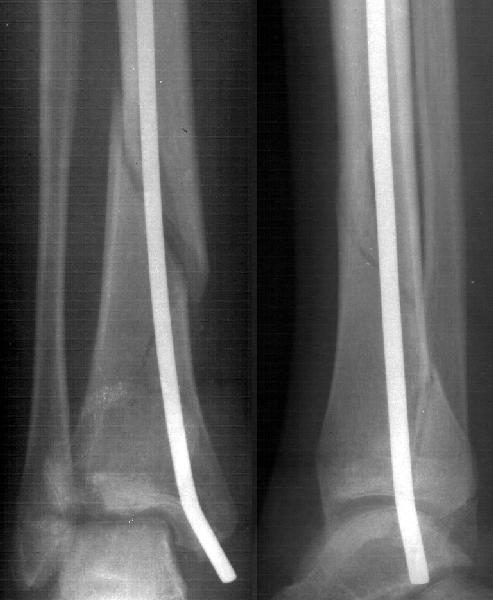

Мне в тоже время совершенно ясно видно по той же КТ, по 4 срезам, расположенным в центре и вверху пленки, что перелома внутренней лодыжки не было, в следующем собщении я приложу увеличенный фрагмент томограммы. А к этому письму прилагаю увеличеный фрагмент послеоперационной рентгенограммы, где выделил отколотый фрагмент

позади внутренней лодыжки. И он, как я вижу, находится между стержнем и тараном. А перелома внутренней лодыжки, и тем более смещения, IMHO

не определяется.